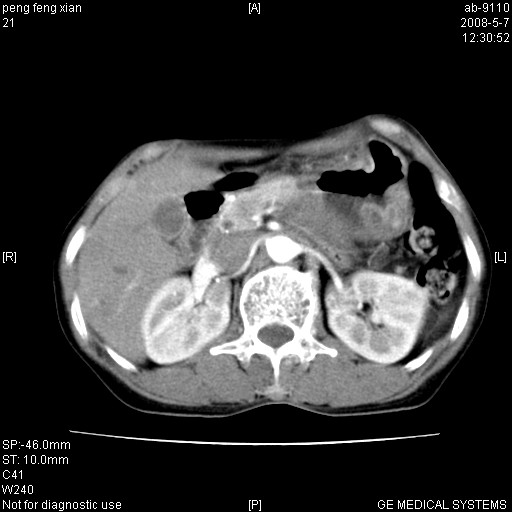

女,56岁。b超左一腹包块,考虑胃肠道肿瘤。

胃壁增厚,左前胸壁局限性隆起,考虑胃癌可能性大,建议做胃镜

典型胃癌胰体尾部受侵。

胃体部胃壁增厚,不均匀性强化,与胰腺分解欠情.

考虑:胃癌,胰腺受侵待除外.

鉴别:胃淋巴瘤(强化不明显)

建议:胃镜检查.